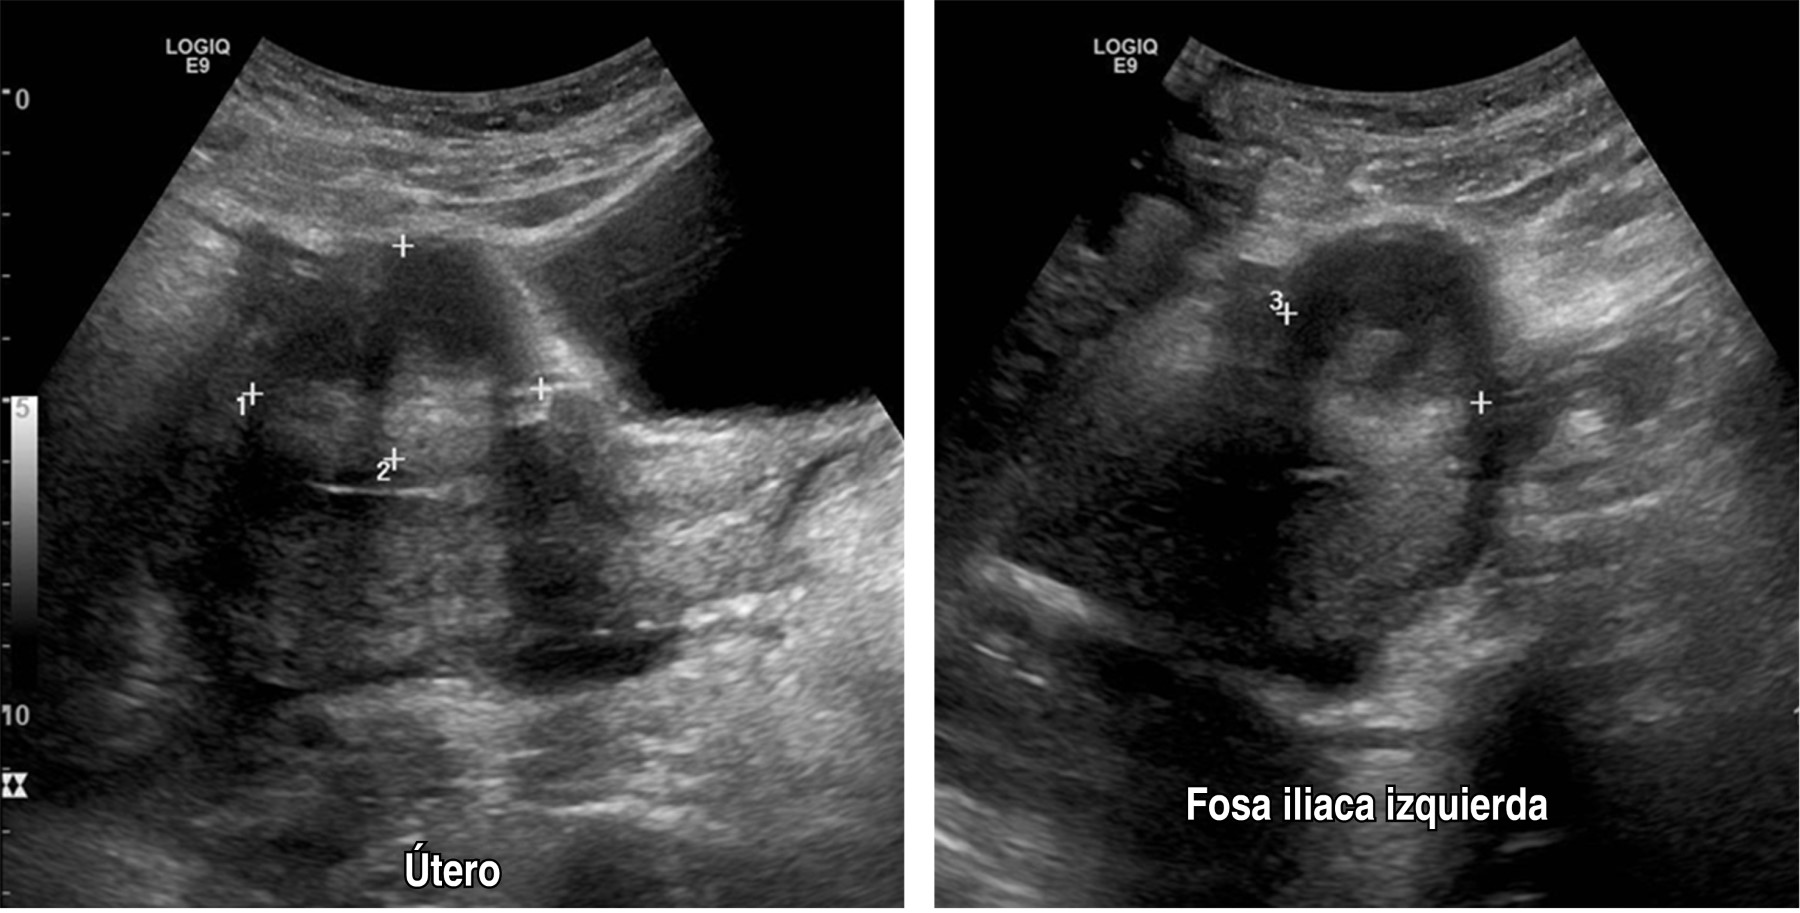

Paciente femenino de 40 años de edad, gesta cuatro, partos tres, con antecedente de estenosis valvular aórtica desde 2017 con manejo quirúrgico a base de colocación de prótesis valvular y acenocumarina hasta el diagnóstico de su último embarazo, durante el cual se suspende anticoagulante oral e inicia enoxaparina. Inicia padecimiento actual al ingresar al servicio de obstetricia con reporte de edad gestacional de 28.5 semanas de gestación (SDG) por última menstruación y de 29.4 por fetometría. Se diagnostica preeclampsia con datos de severidad, por lo que se decide realizar cesárea tipo Kerr y oclusión tubaria bilateral con técnica de Kroener, reportando 350 cm3 de sangrado, obteniendo producto único vivo, masculino, 31.5 semanas por Capurro, Apgar 7/8, con labio y paladar hendido. Egresa al quinto día requiriendo transfusión de hemoderivados en su postquirúrgico inmediato. Veintiún días después reingresa por sangrado abundante y fétido a través del abordaje quirúrgico, se hace curación y se evidencia defecto de pared abdominal, por lo cual se decide realizar ultrasonido, con hallazgos de defecto de pared anterior del abdomen en porción cefálica de la herida a través del cual protruyen asas intestinales (Figuras 1 y 2), en tomografía de abdomen se identifica colección heterogénea no medible en tercio medio y caudal de herida a nivel del plano subcutáneo, así como colección de pared gruesa en cavidad pélvica y fosa iliaca izquierda (Figura 3).

Figura 2